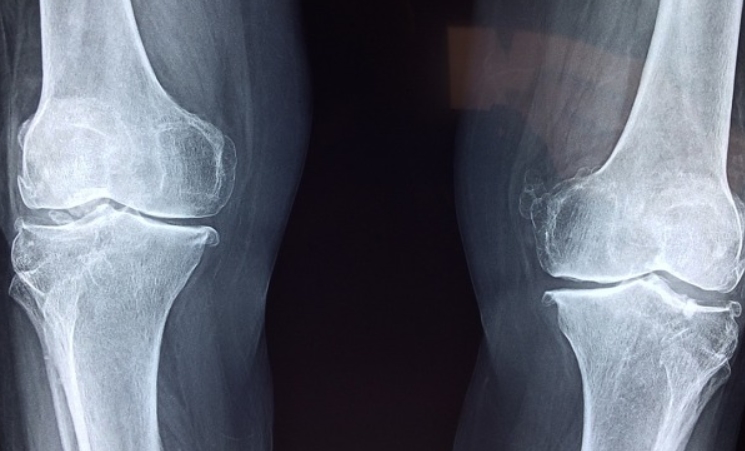

무릎통증원인 퇴행성 관절염이 진행되면 연골이 거의 없어져 뼈끼리 부딪히면서 심한 통증이 생길 수도 있습니다.

무릎 관절염 증상

관절염이 생기면 무릎이 뻣뻣해지고, 움직일 때마다 불편함이 커질 수 있습니다. 무릎에서 뚝뚝 소리가 나요 증상이 진행될수록 걷는 것도 힘들어질 수 있습니다.